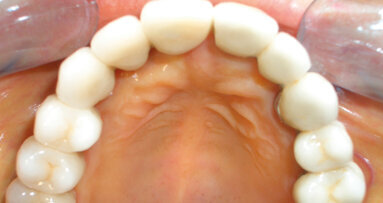

Nell’arcata superiore il paziente è totalmente edentulo e portatore di protesi totale. All’anamnesi, risulta essere stato sottoposto due anni prima a intervento di angioplastica con installazione di 6 stent coronarici a causa di un infarto miocardico. A seguito dell’evento infartuale, il paziente assume Ticlopidina e farmaci beta-bloccanti per il controllo della pressione arteriosa. Il soggetto non è fumatore da due anni. Considerato il quadro clinico-anamnestico, si stipulano due piani di trattamento alternativi.

Il primo prevede le estrazioni degli elementi dentari residui e la fabbricazione di una protesi totale inferiore; il secondo consiste invece nel posizionamento di quattro impianti interforaminali e la successiva consegna di una protesi totale inferiore su barra. Il paziente, informato dei rischi e dei benefici delle due opzioni, sceglie la soluzione implantare. Pochi giorni prima dell’intervento il paziente viene preparato da un punto di vista parodontale sottoponendolo a sedute di igiene orale, curettaggi, istruzione e motivazione all’igiene orale, al fine di poter eseguire la chirurgia implantare in un contesto di tessuti parodontali il più possibile disinfiammati. Alla rivalutazione si osserva un netto miglioramento della situazione parodontale, seppure permanendo l’alto grado di mobilità degli elementi 4.4, 3.4, 3.5 (Figg. 2, 3).